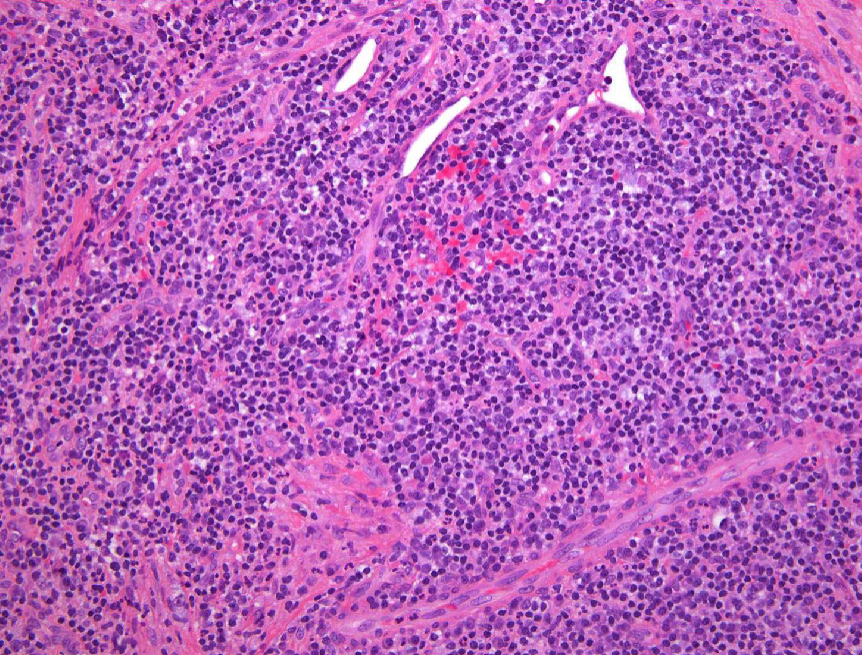

2 histopath features of periapical granulomas

granulation tissue surrounded by fibrous connective tissue

lymphocytic infiltrate may be intermixed with neutrophils, plasma cells, histiocytes, and occasionally mast cells or eosinophils

2 histopath features of periapical abscesses

acute inflammatory cells, cellular debris, necrotic material, and bacterial colonies

Phoenix abscesses may include soft tissue component